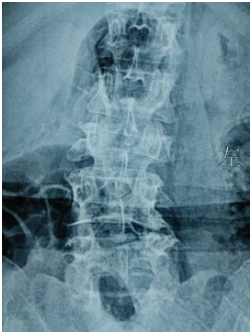

(上圖為患者術(shù)前X片)